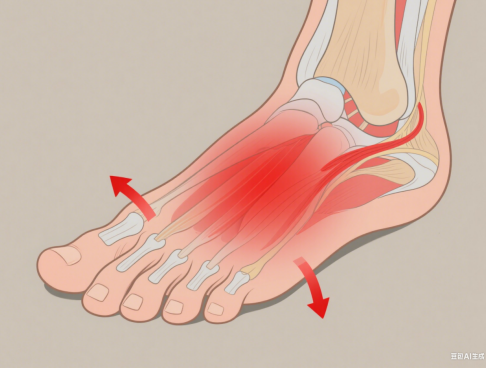

您是否曾在清晨下床的第一步,感到脚后跟有一阵尖锐的刺痛?或者长时间走路、站立后,足底感到酸胀不适?如果有,那么您很可能正在经历一种十分常见的足部疾病——足底筋膜炎。它虽然不是危及生命的大病,但却能严重影响生活质量,让人“步步惊心”。什么是足底筋膜炎?简单来说,足底筋膜炎是足底筋膜(脚底的一条韧带)发生的无菌性炎症和退化。它像一根强大的弓弦,从您的脚跟骨(跟骨)延伸至五个脚趾根部,...